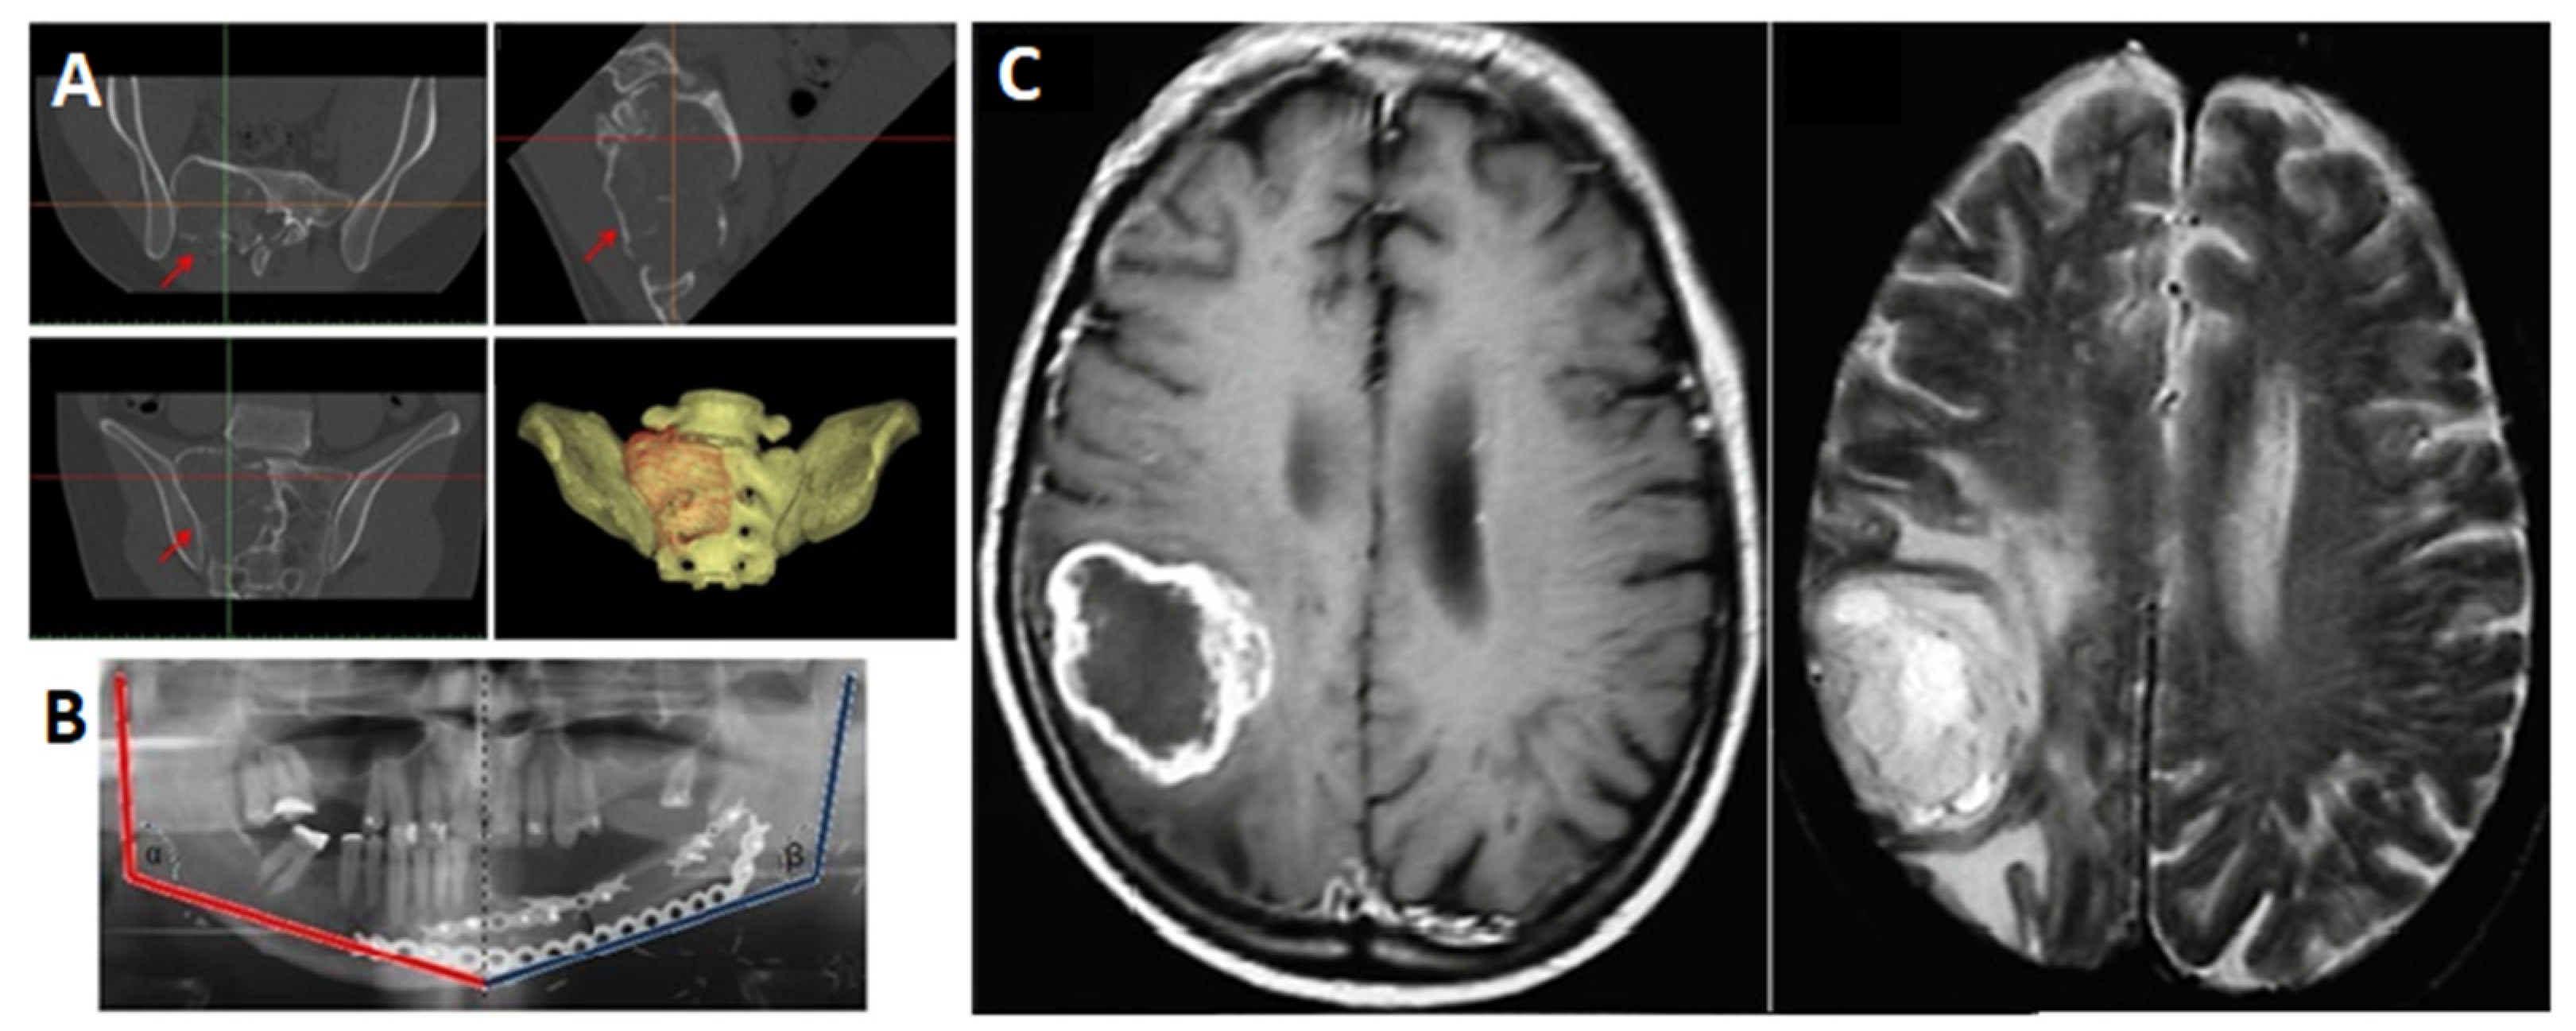

| 16 | W. Mussi et al. [27] | 2020 | Neurology | PLA PLA wood-loaded Silicone rubber—The SmoothOn EcoFlex 00-50 Silicone rubber—DragonSkin 10 | MakerBot Replicator 2X (FFF) Manual casting | Skull Brain Tumour Tentorium Flax | Simulated operations Training models |